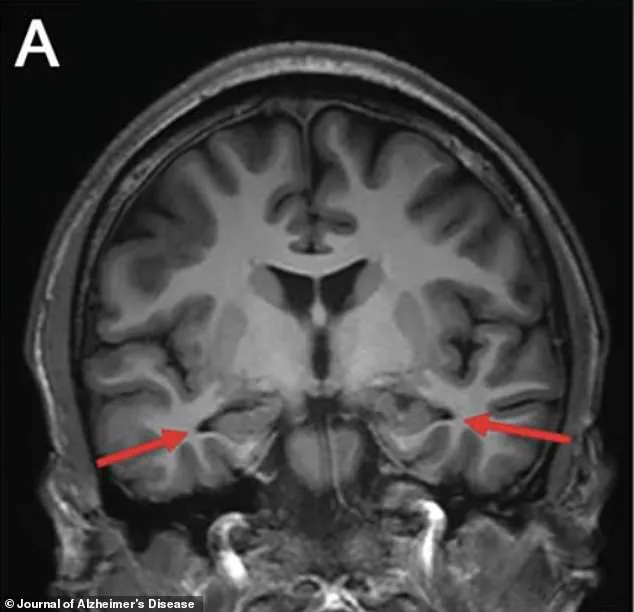

In 2022, advanced brain scans revealed a chilling detail: significant shrinkage in the hippocampus, a region of the brain critical to memory formation and one of the first areas targeted by Alzheimer’s.

An MRI of the brain revealed a chilling revelation: the hippocampus, the region responsible for memory formation, was visibly shrinking.

Other scans confirmed reduced activity in the parietal and temporal cortices, areas critical for memory and cognitive processing.

The images, marked with arrows pointing to the affected regions, offered a stark visual representation of the brain’s deterioration.

These findings were a red flag, suggesting a progressive and potentially irreversible condition.